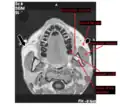

- Horizontal MRI scan of a head, at the level of the mandibular teeth, showing the masseter muscle and neighbors.